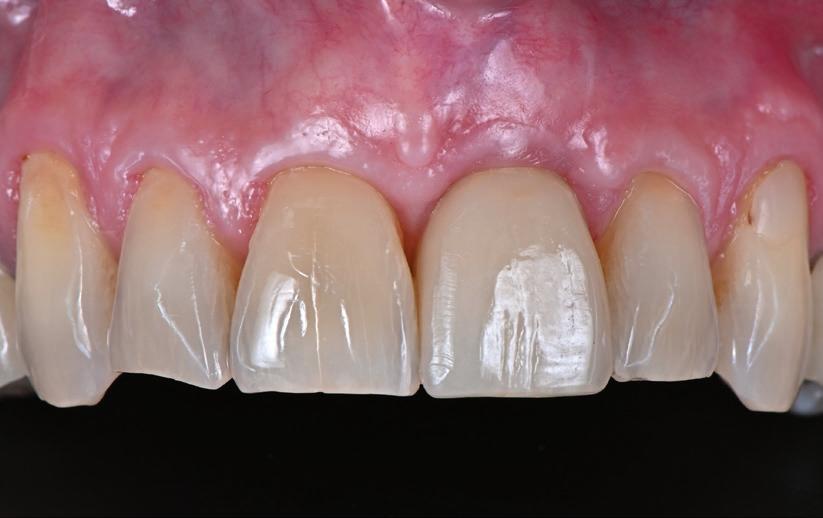

REABILITAREA implanturilor în zona estetică. Acest articol detaliază două cazuri rezolvate prin tehnica extracției parțiale, finalizate fără grefarea compartimentului dintre implant și scut, și monitorizate cinci ani, dovedind stabilitatea volumetrică a țesuturilor moi și dure în timp.